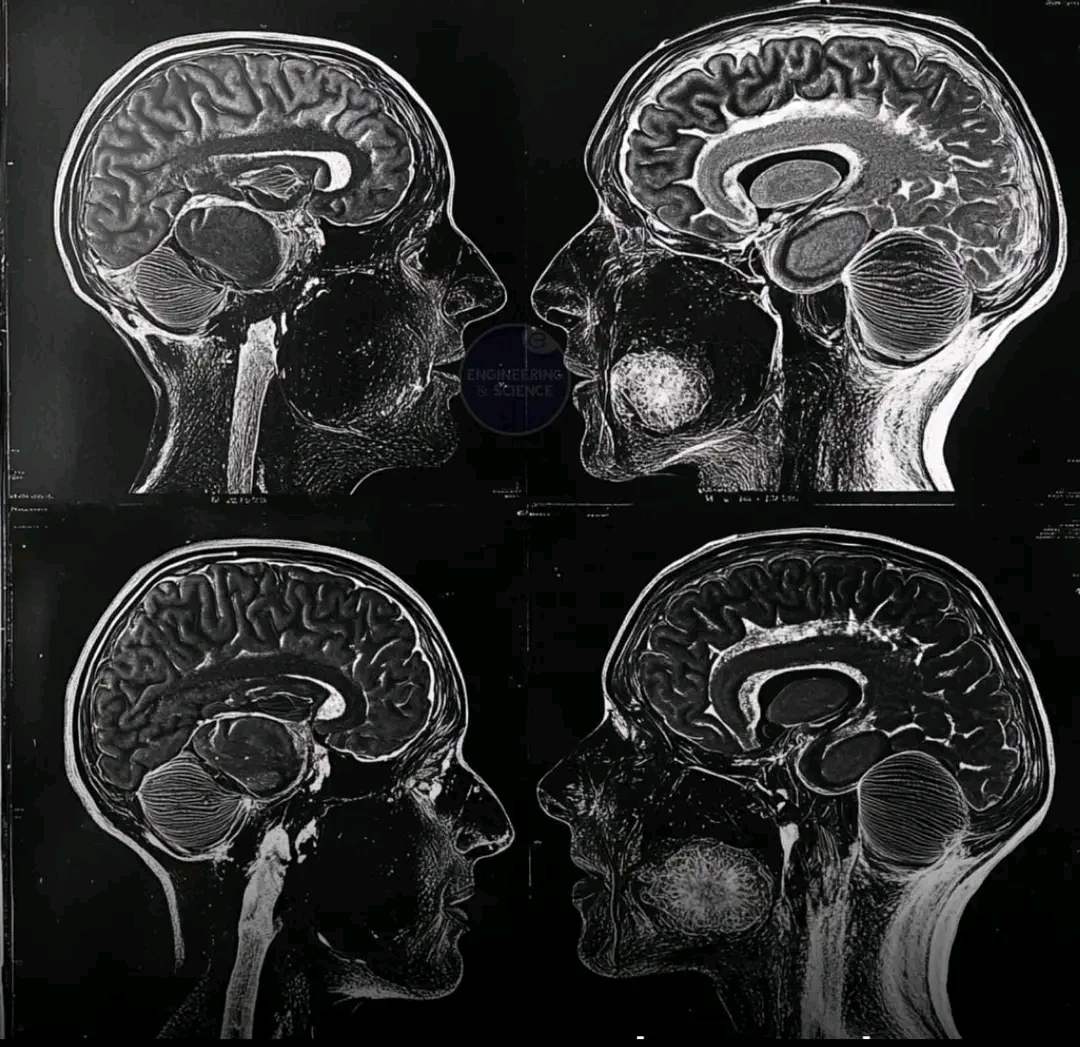

ตามที่เปิดเผยโดยเทคโนโลยีสแกนสมองขั้นสูง ผลการศึกษาชี้ให้เห็นว่าการอดอาหารสามารถเพิ่มความยืดหยุ่นของระบบประสาท สมรรถภาพทางการรับรู้ และความกระจ่างแจ้งของจิตใจ ซึ่งอาจช่วยลดความเสี่ยงของโรคทางระบบประสาท เช่น อัลไซเมอร์และพาร์กินสัน ด้วยการเปลี่ยนแปลงวิถีประสาทและส่งเสริมการสร้างเซลล์ใหม่ การอดอาหารอาจเป็นปัจจัยสำคัญต่อสุขภาพสมอง ความอายุยืนยาว และความยืดหยุ่นทางการรับรู้ เนื่องจากความสนใจในการแฮ็กทางชีวภาพ วิทยาศาสตร์การมีอายุยืนยาว และสุขภาพด้านเมตาบอลิซึมเพิ่มมากขึ้น การอดอาหารจึงกลายเป็นวิธีการที่ได้รับการสนับสนุนทางวิทยาศาสตร์ในการเพิ่มประสิทธิภาพการทำงานของจิตใจและความเป็นอยู่โดยรวม